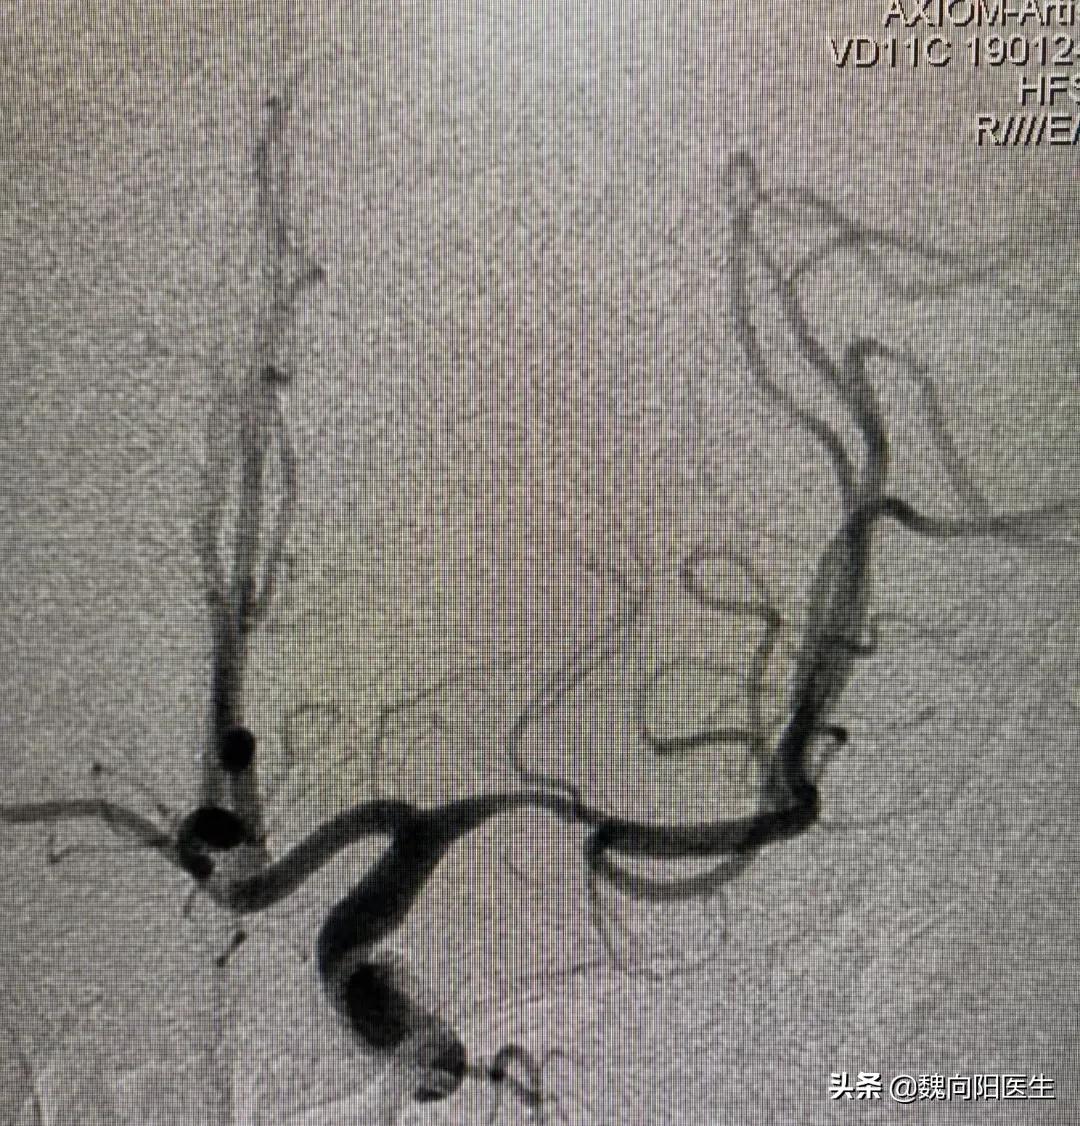

有症状的颅内动脉粥样硬化性动脉狭窄是卒中最常见的原因之一,卒中复发的风险较高。

很多人在发现脑动脉狭窄之后,会问医生需不需要做血管支架,甚至有些医生会建议患者做血管支架,以预防脑梗死发生。

@魏向阳医生 建议: 对于颅内动脉狭窄,建议首选药物及运动等行为方式来预防脑梗死(严格内科保守治疗),不建议立即放入血管支架,预防可能的脑梗塞。

对于经过严格的内科保守治疗无效的患者,仍反复发生脑梗死,且梗死部位与狭窄血管密切相关的,再考虑血管支架植入治疗。